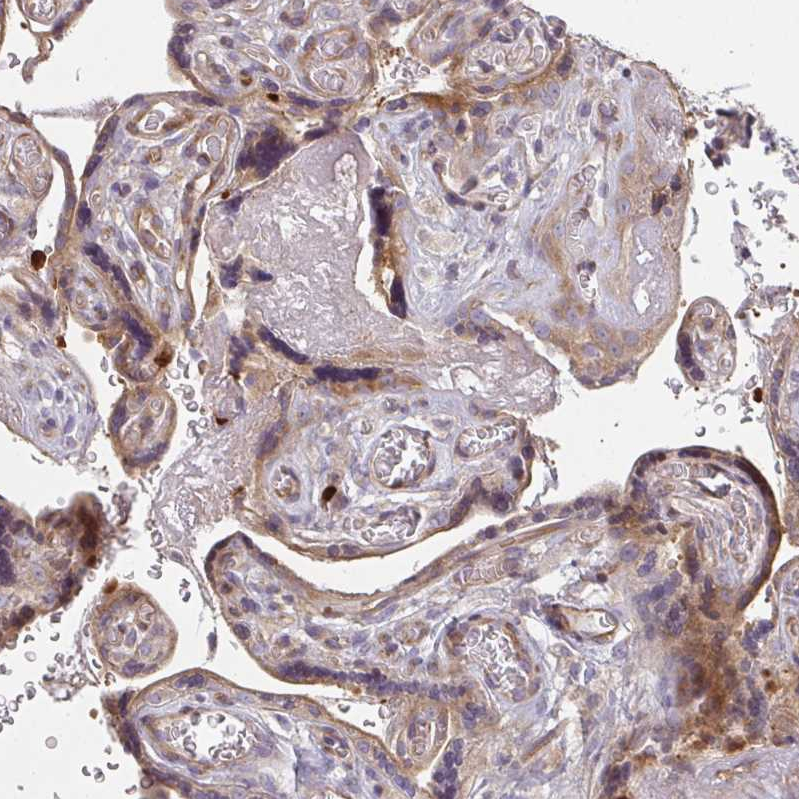

Immunohistochemical staining of human placenta shows moderate cytoplasmic positivity in trophoblastic cells.